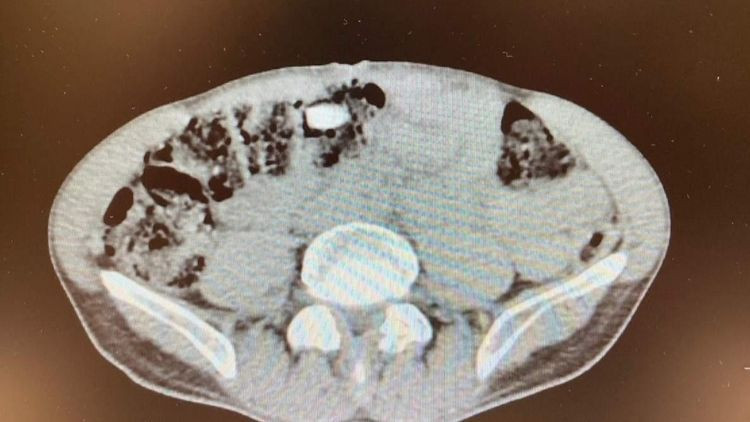

Polise, uyuşturucu yuttuğunu itiraf eden İran uyruklu zanlı, iç beden muayenesi için hastaneye götürüldü. Röntgeni çekilen şüphelinin kapsül haline getirilen uyuşturucu hapları yuttuğu belirlendi.

MİDESİNDEN 3 KAPSÜL ÇIKARILDI

Denizli Devlet Hastanesi'nde gözlem altında tutulan zanlının midesinden 3 kapsül halinde 15 uyuşturucu hap çıkarıldı. Gözaltına alınan zanlı, emniyetteki işlemlerinin ardından sevk edildiği adli makamlarca tutuklandı.